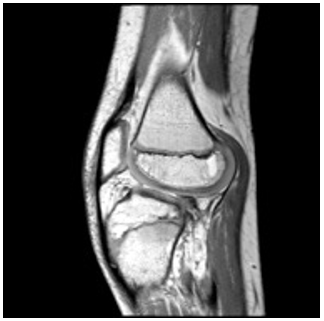

El segundo caso corresponde a un paciente de 11 años de edad con inestabilidad de la rodilla y acortamiento del miembro inferior izquierdo en estudios prequirúrgicos de la hemimelia de peroné. Se le realizó una resonancia magnética de rodilla con signos de inestabilidad de la articulación de la rodilla, por ausencia completa del ligamento cruzado anterior (figura 3), así como inestabilidad de la patela.

Se observa agenesia del ligamento cruzado anterior con translación anterior de la tibia, patela baja e inserción baja del tendón patelar